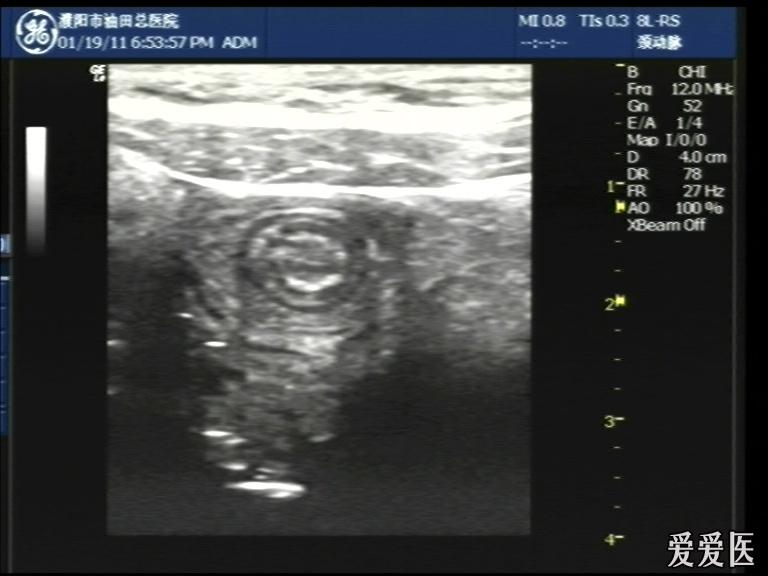

超声检查:于下腹部可见“双环征象”,双环重叠长约6mm,检查期间观察可见肠蠕动;CDFI:未见明显异常血流信号。

超声提示:下腹部双环征,考虑肠套叠可能,请结合临床

“套筒征”、“同心圆征”,很清晰,很经典!

好图,同心圆征。清晰